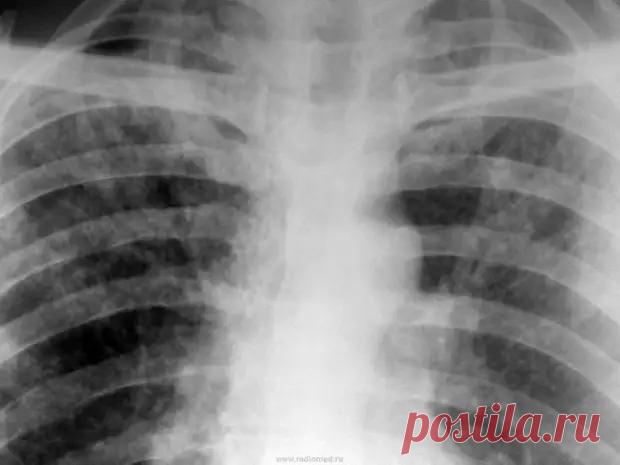

Видно ли туберкулез на снимке рентгена? - ПолонСил.ру - социальная сеть здоровья - 23 июля - 43489617743 - Медиаплатформа МирТесен